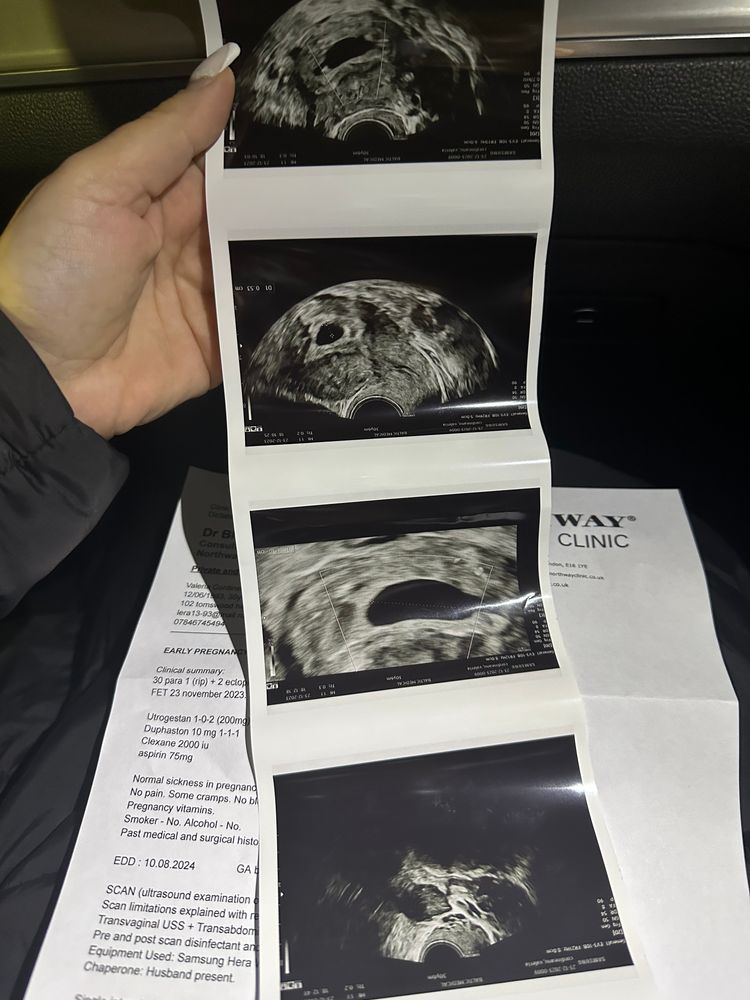

Здравствуйте девочки - вопрос возможно глупый но ситуация странная. Итак, в прошлую субботу мне исполнилось 3 недели после 5-дневного переноса эмбрионов. Итак, сканирование показало эмбрион размером 1,9 мм и плодное яйцо диаметром 9,5 мм. Я сдавала ХГЧ 4 раза за этот период и все в порядке. Вчера сделала сканирование (то есть через 4 недели после переноса) и уже виден только мешок 15,3 мм, а эмбрион исчез? Может ли быть такое - одну неделю эмбрион существует, а вторую неделю чудесным образом исчезает? У меня не было ни кровотечения, ни болей в животе. Прикрепляю фото первого скана с эмбрионом и второго вчерашнего скана без эмбриона. Врач рекомендовал мне продолжить лечение до следующего четверга и сделать еще одно сканирование через 5 недель после переноса. Любые предложения и советы будут оценены по достоинству. Большое спасибо

это и скан и анализ крови в один день

это и скан и анализ крови в один день

Ангелина, и сейчас прикреплю и рапорт где есть эмбрион

Ангелина, и сейчас прикреплю и рапорт где есть эмбрион